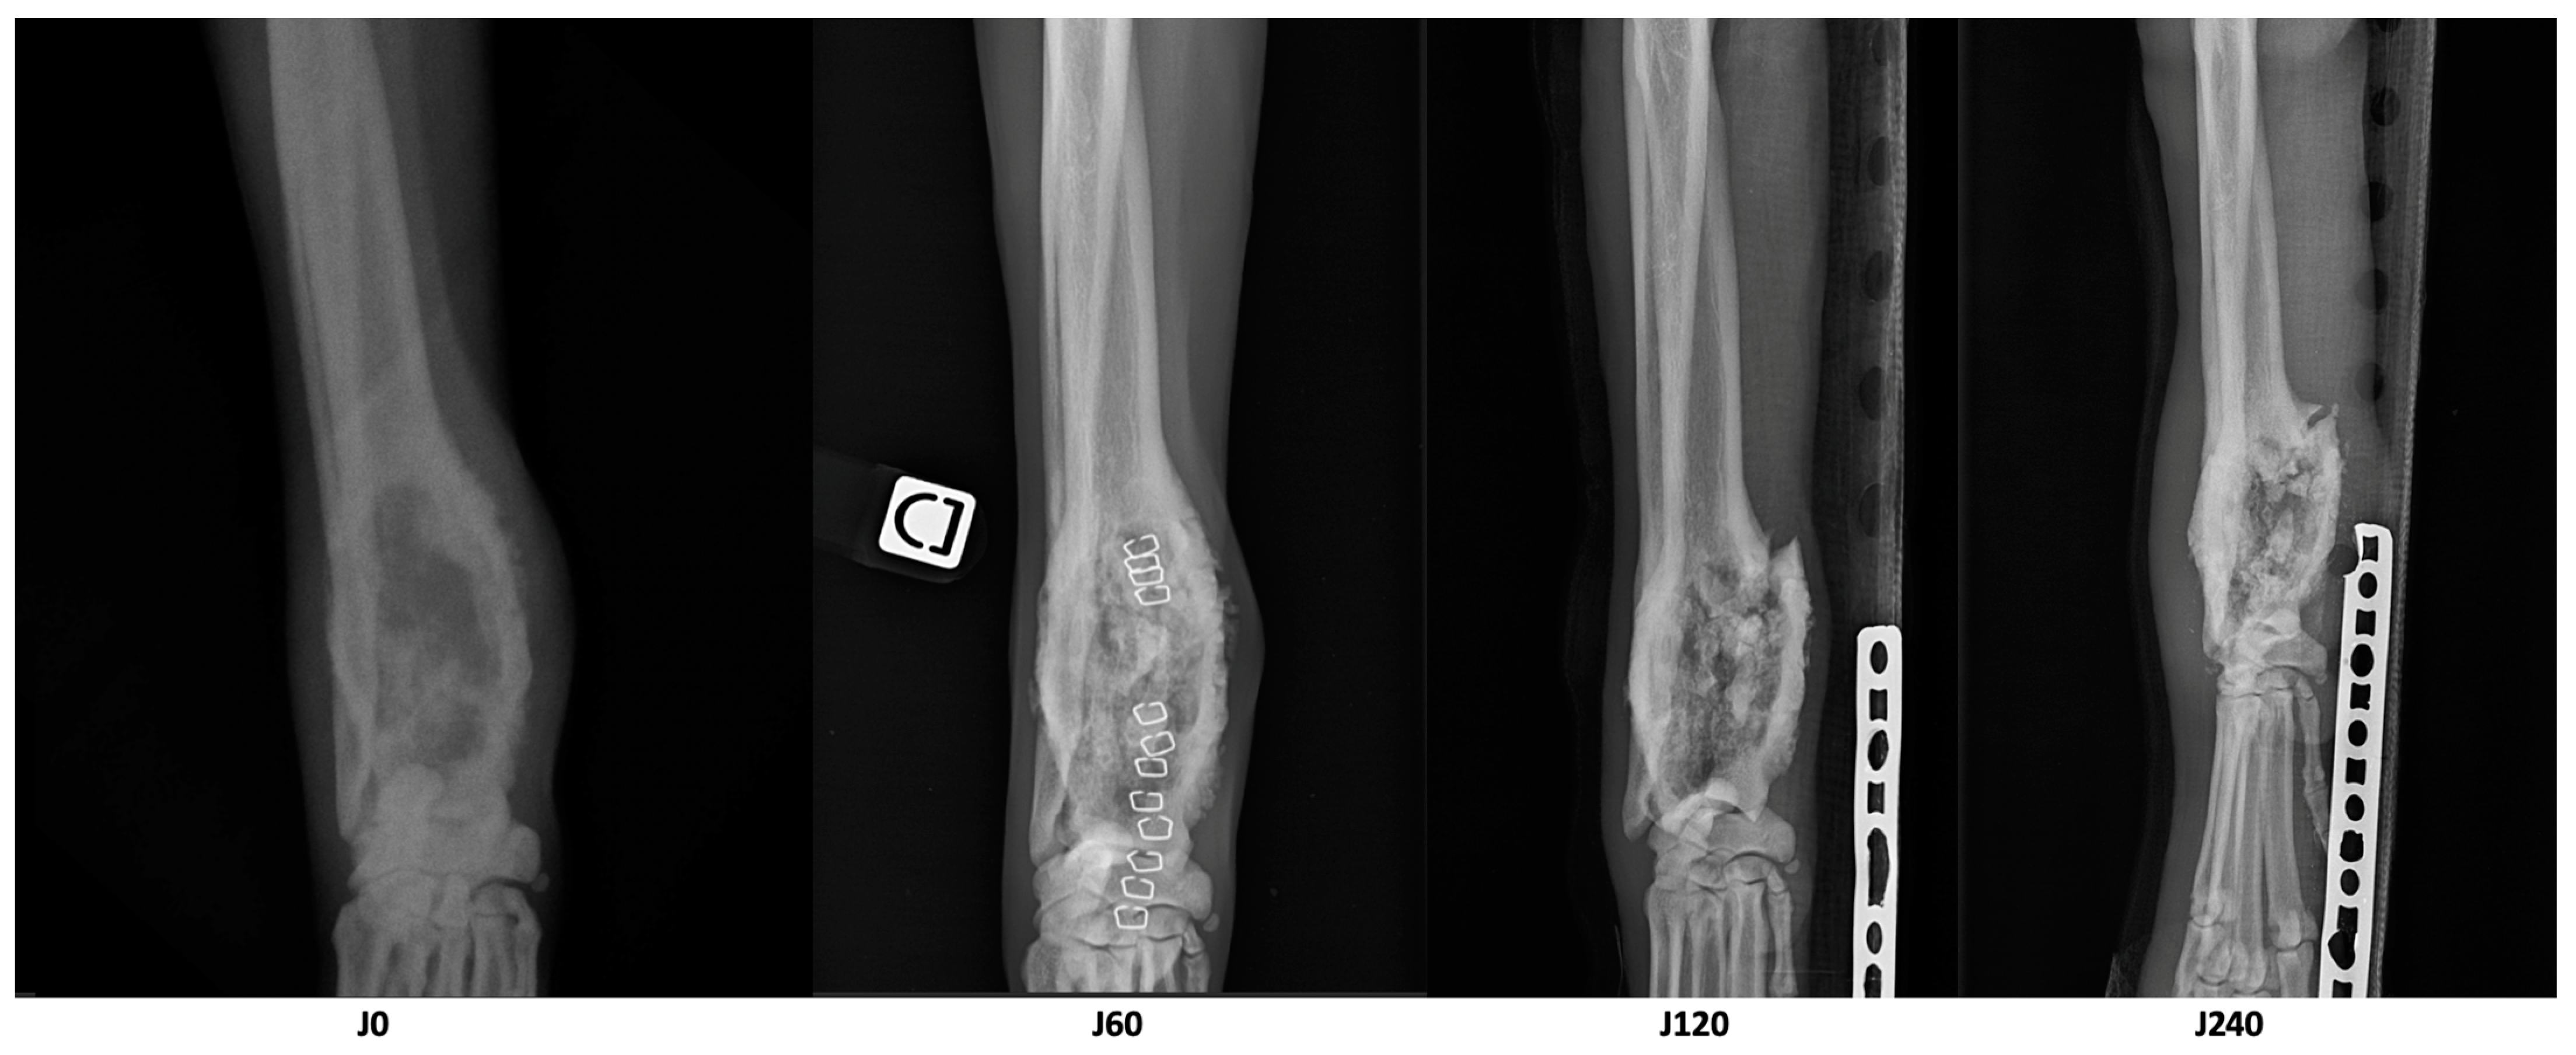

| Parameter | D0 | D60 | D210 | Variation D60/D0 | Variation D210/D0 |

|---|---|---|---|---|---|

| Longest diameter of the osteolytic area (cm) | 8.1 | 6.7 | 6.1 | −17% | −25% |

| Volume of dense tissue in the osteolytic area (cm3) | 18.8 | 21.1 | 17.5 | +12% | −7% |

| Volume of the cortical bone of the area of interest (cm3) | 8.2 | 10.6 | 7.7 | +29% | −6% |